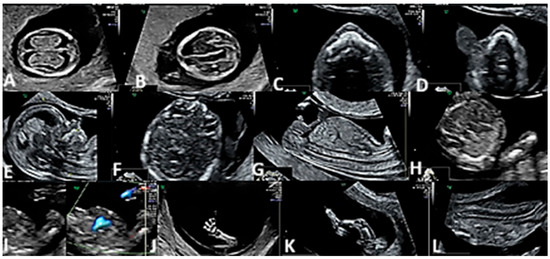

| Nervous system | 23 | 23/58 (39.6%) | <0.01 |

| Holoprosencephaly | 11 | 11/58 (18.9%) | |

| Anencephaly | 7 | 7/58 (12%) | <0.01 |

| Exencephaly | 5 | 5/58 (8.62%) | <0.01 |

| Face | 7 | 7/58 (12%) | |

| Cleft lip only | 4 | 4/58 (6.89%) | <0.01 |

| Cleft palate only | 2 | 2/58 (3.4%) | |

| Cleft lip and palate | 1 | 1/58 (1.7%) | |

| Thorax and abdomen | 12 | 12/58 (20.6%) | |

| Omphalocele | 9 | 9/58 (15.5%) | |

| Gastroschisis | 3 | 3/58 (5.17%) | |

| Limbs | 2 | 2/58 (3.4%) | |

| Club foot | 1 | 1/58 (1.7%) | |

| Polydactyly | 1 | 1/58 (1.7%) | |